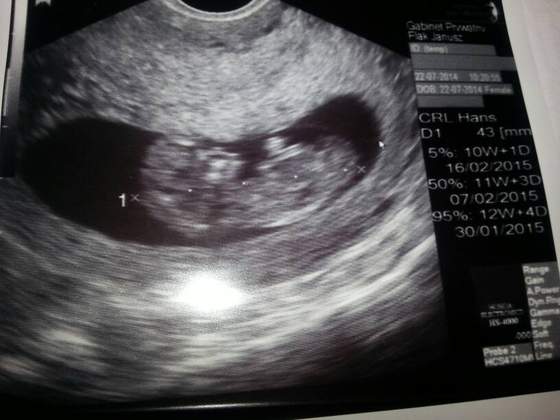

część. Byliśmy wczoraj u lekarza na usg, wszystko w porzątku tylko maluszek się nie chciał ustawic do zmierzenia przeziernosi,ale wszystko jest dobrze. Maleństwo przyśpieszylo troszkę bo powinno byś 11 tyd i 4 dni a ono jest duże na 12tyg i 1 dzień więc termin przesuną sie na 30 styczeń. Pozdrawiam i życzę samych dobrych wyników.

Dziewczynki ja po wizycie maluszek odpowiada 12 tyg. Dlugosc ok 5cm. Wszystko pieknie sie rozwija. 28 prenatalne w moim szpitalu i kolejna wizyta 19.08.

• 1406039700989.jpg

1406039700989.jpg

27,1 KB · Wyświetleń: 73